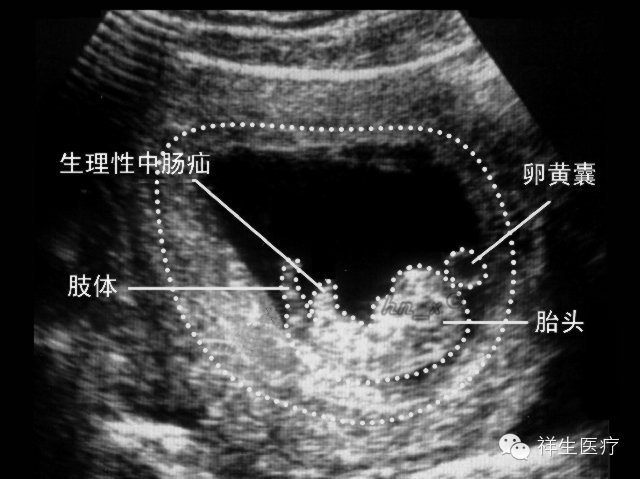

4.孕8周:初具人形,各部分迅速发展,头颅、躯干、四肢显示越来越清楚。